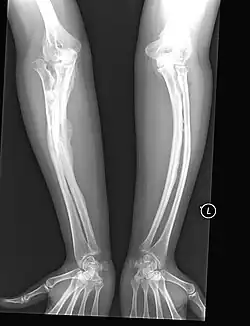

Orthopedic

The main symptom of osteogenesis imperfecta is fragile, low mineral density bones; all types of OI have some bone involvement.[5] In moderate and especially severe OI, the long bones may be bowed, sometimes extremely so.[28] The weakness of the bones causes them to fracture easily—a study at the Endocrine Unit at the National Institute of Child Health in Karachi, Pakistan found an average of 5.8 fractures per year in untreated children.[29] Fractures typically occur much less after puberty, but begin to increase again in women after menopause and in men between the ages of 60 and 80.[1]: 486

Diagnosis is typically based on medical imaging, including plain X-rays, and symptoms. In severe OI, signs on medical imaging include abnormalities in all extremities and the spine.[97] As X-rays are often insensitive to the comparatively smaller bone density loss associated with type I OI, DEXA scans may be needed.[5]: 1514